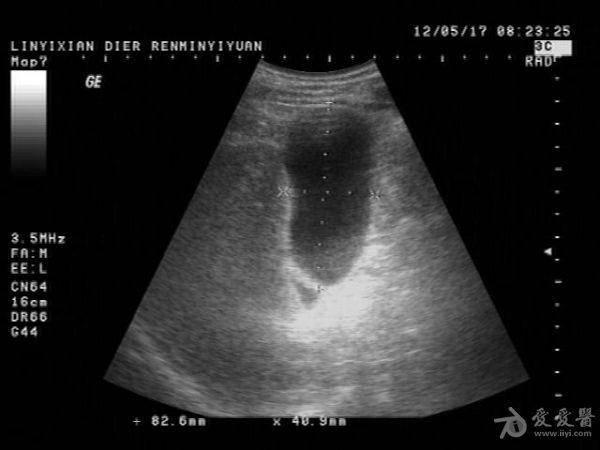

患者男性,57岁,十多年前曾患“肝炎”,近一年在它院曾诊断为:肝硬化。一月前在市医院治疗发现有腹水形成并发现有“腔梗”。古来我院就诊。B超提示:肝脏病理声像(肝光点增粗、肝硬化声像)胆囊图像如图。腹盆腔未及游离暗区回声。

这个胆囊颈部的暗区可以称“胆囊憩室”吗?